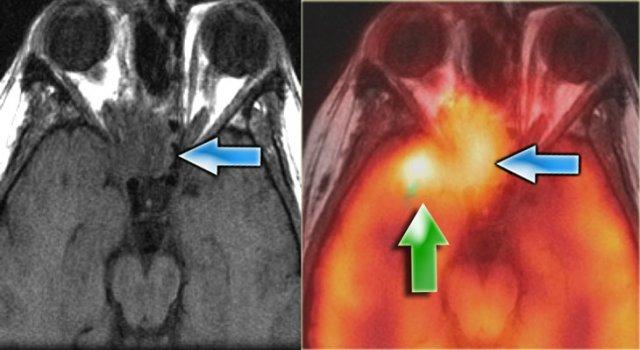

Bệnh nhân bên trái đã được phẫu thuật cắt bỏ ung thư biểu mô.

Hiện tại ghi nhận tình trạng tái phát (mũi tên xanh lam trên ảnh MRI và ảnh hợp nhất).

Tuy nhiên, mũi tên xanh lá chỉ vào các thay đổi mô sau xạ trị.

Bên trái là hình ảnh của bệnh nhân đã được phẫu thuật cắt bỏ sọ-mặt trước đó (mũi tên vàng) vì ung thư biểu mô kém biệt hóa.

Bệnh nhân này được điều trị bằng hóa-xạ trị.

Chuỗi xung T2W bên trái cho thấy hình ảnh u tái phát trong sọ.

Tiếp tục xem các ảnh có tiêm thuốc tương phản từ.

Trong những trường hợp như thế này, tổn thương tái phát thường biểu hiện với các hình thái bất thường, điển hình như các ổ di căn màng cứng lan rộng như được thấy ở đây.